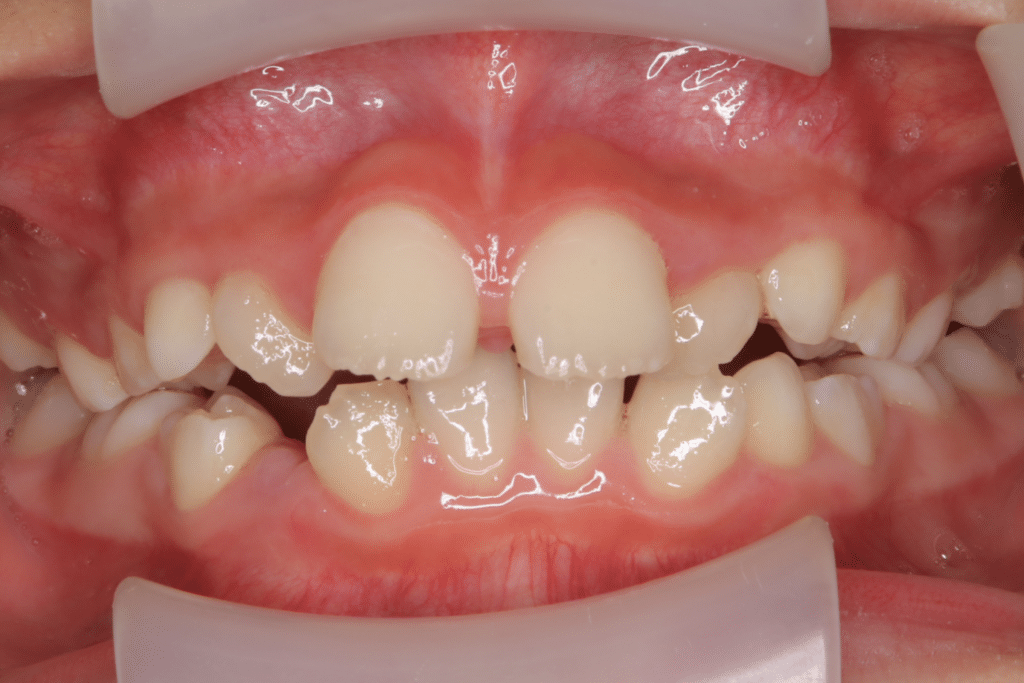

叢生(そうせい・デコボコ)についての症例1

叢生 症例 Case 1

7歳9ヶ月から開始

主訴:デコボコ、ガタガタに噛んでいる噛み合わせを治したい

診断名:叢生(そうせい)

治療装置:拡大床(床矯正)とインビザライン+筋機能療法を併用し治療

(開始後0ヶ月)まずは拡大床/床矯正にて顎の狭さを改善する方向で進める。患児の保護者と相談の結果、いきなり歯を動かすのではなく、まずは顎骨の狭さの改善(土台の改善)から進めることに、装着時間は13〜17時間を目指して装着してもらった(拡大床+筋機能療法も併用)

本格的に歯を動かす前に、顎骨の改善(土台の改善)を行っておくことで、後戻りのリスクを下げられるため上記の方針で、患児の保護者と合意

叢生

(7歳9ヶ月)

開始後0ヶ月